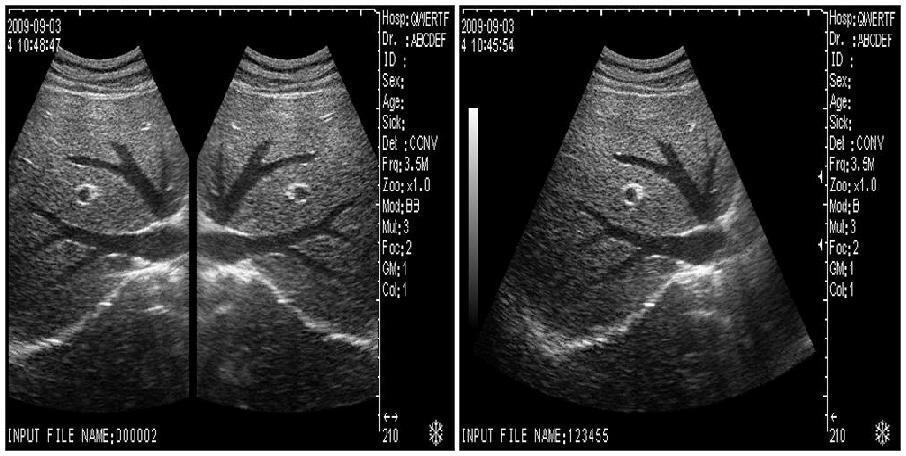

Model: HIGH RESOLUTION

Display modes: B, B+B, B+M, M, 4B

Scanner depth: 230mm

Gray scale: 256

Image conversion: up/down, left/right, black/white

Local zoom: 4(can be used at frozen/real-time)